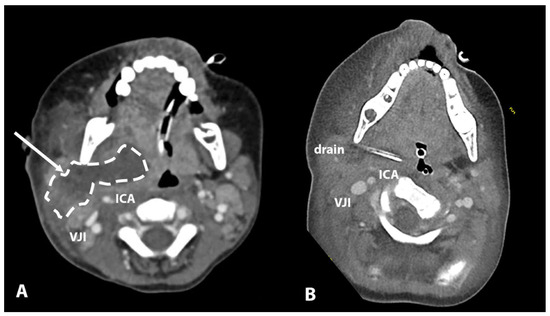

| 6 | 3 years | Parapharyngeal | Conglomerate of enlarged level II lymph nodes, area of collection in level II lateral to ICA | Major parapharyngeal collection 53 × 25 × 45, lateral and anterior to ICA | / | Intubation | Lateral | CT |

| 6 | 3 years | Parapharyngeal | Lateral | Intubation | Transcervical incision | Image guidance | Staph. aureus | Piperacillin/Tazobactam | 4 |